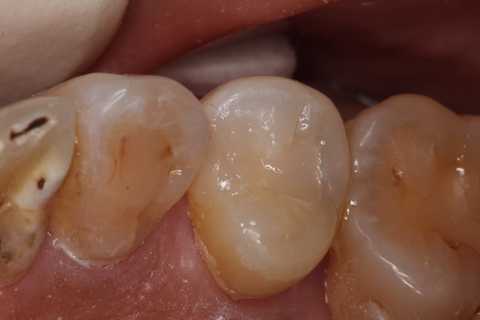

40代女性、左上5、冷水痛+

では時系列でどうぞ